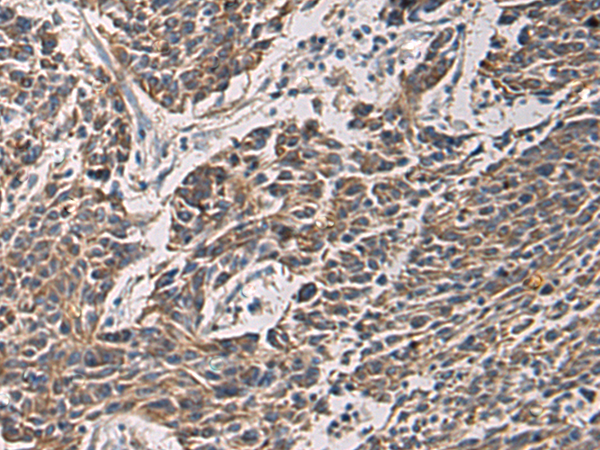

分类: 科研抗体货号: P10442别名: IF; GIF; INF; IFMH; TCN3应用: IHC反应种属: Human, Mouse, Rat